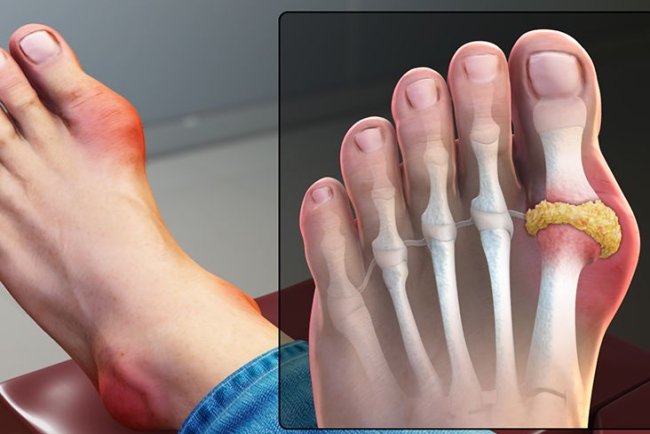

How do big toe joint problems occur and what measures c...

While it may not seem like a big toe issue, having one can take control of your life. The joints are so swollen that they're unfit...